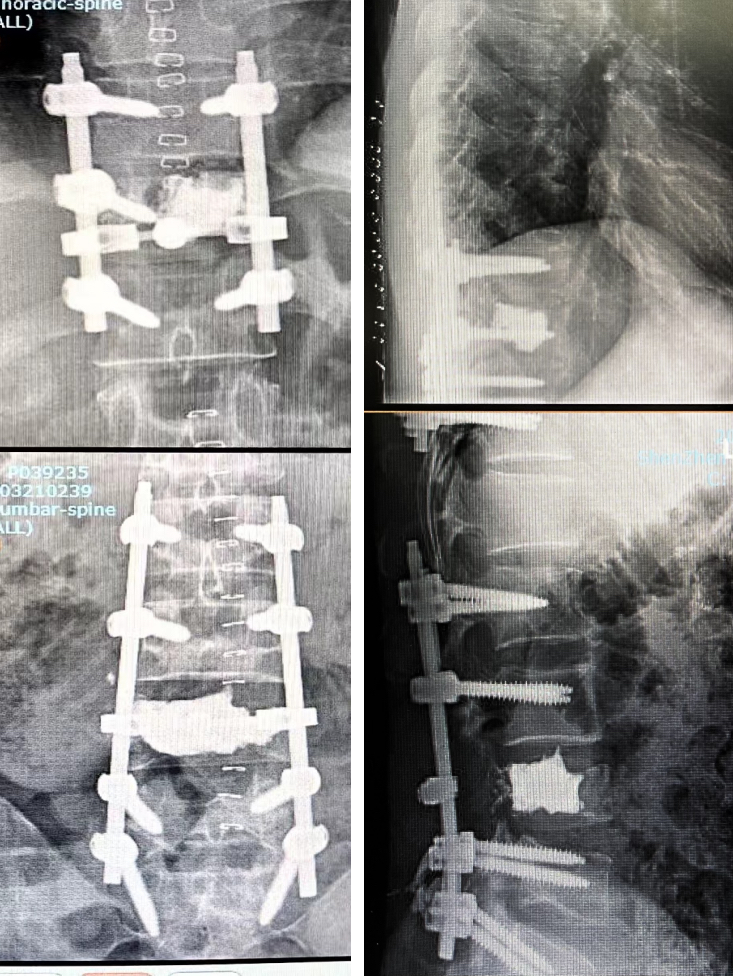

术前一天行介入下栓塞;次日行T11、L4节段分离手术,胸椎短节段固定(移动窗、小切口),腰椎长节段固定(间隙固定),术中出血量不足1000ml。

术中及术后影像:

患者术后2周即可下地行走。